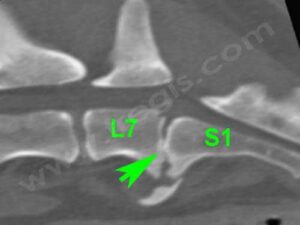

Scanner de la région lombo-sacrée d’un chien atteint de discospondylite (spondylodiscite). L’espace intervertébral entre L7 et S1 est collabé, une prolifération osseuse ventrale est présente.

Discospondylite (ou spondylodiscite)

C’est une affection peu fréquente. Néanmoins, une prédisposition du Berger allemand est rapportée, avec un Odds ratio de 2,6 par rapport aux chiens de races croisées. La discospondylite (ou spondylodiscite), touche plutôt les chiens d’âge jeune ou moyen et les mâles sont deux fois plus atteints que les femelles. (Burkert et al. 2005)